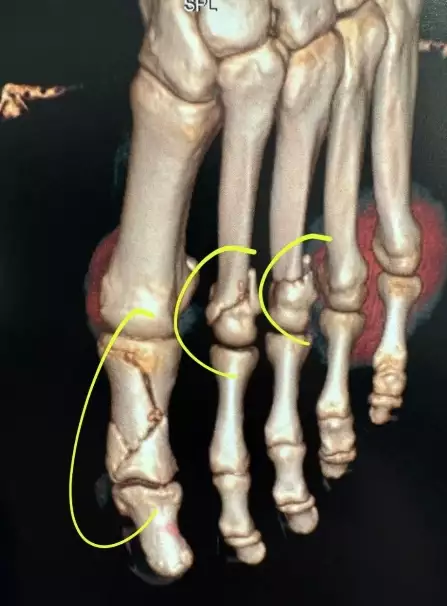

"Chtěl jsem odejít, protože na tenhle výkon nejsem pyšný. Vím, jak jsem se nadřel, ale rozhodně jsem to nedokázal prodat. Hned na začátku zápasu jsem si poranil nohu, což mě dost limitovalo. Bolelo to," postěžoval si Gane po souboji a uznal, že to ani zdaleka nebyl jeho nejlepší výkon. Limitovalo ho totiž zranění a není se čemu divit. Rentgen totiž ukázal tři zlomené prsty, což už je sakra hodně.